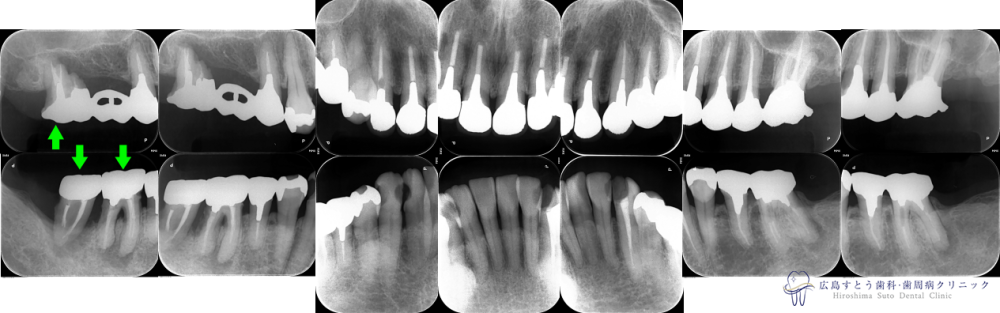

インプラントの症例

Case1

Before

初診時の状態

初診時の状態

After

メンテナンス開始時

メンテナンス開始時

術前

初診時の状態:矢印の歯は予後不良のため抜歯になりました

右上の抜歯後の状態:歯肉が陥凹してしまっています

治療終了後のレントゲン写真

| 治療名 | GBR(骨再生誘導療法)、インプラント治療(3本分) |

|---|---|

| 治療説明 | 右上と右下の奥歯に歯茎の腫れがあり、診査の結果、歯根破折および重度歯周炎により抜歯することになりました。抜歯後はインプラント治療を希望されたため、抜歯後、失われた歯槽骨を造成するためにGBRを行い、インプラント治療を行いました。 |

| 治療回数・期間 | 約36ヶ月 (歯周基本治療、抜歯、GBR、インプラント治療、矯正治療、補綴治療、ホワイトニング含む) |

| 副作用とリスク | 歯周外科後には一時的に術後に腫れや仏痛や出血が発現することがあります。 治癒の状態によって治療期間が長くかかる場合があります。 |

| 料金 | 155.9万円 (ただしGBR、インプラント治療の部分のみ。他の被せ物や矯正治療、ホワイトニングは別途費用がかかります。) |